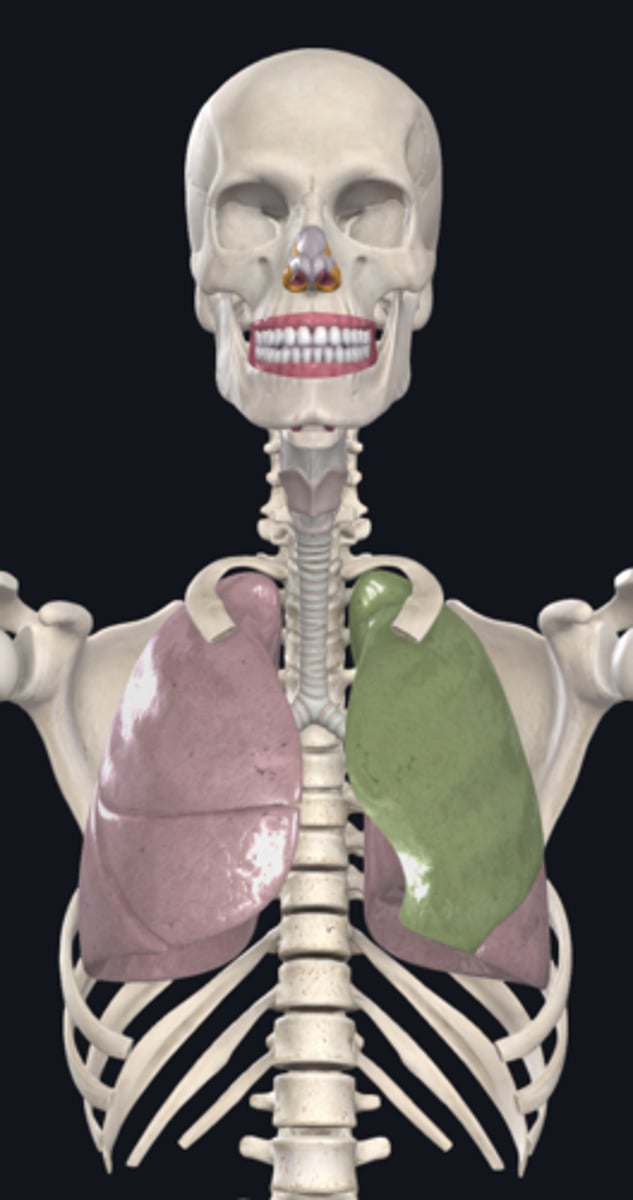

right lung

superior lobe of right lung

middle lobe of right lung

inferior lobe of right lung

left lung

superior lobe of left lung

inferior lobe of left lung

base (diaphragmatic surface)

apex